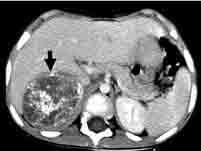

问题 婴儿期最常见的肿瘤是()

选项 A.肾母细胞瘤 B.神经母细胞瘤 C.视网膜母细胞瘤 D.肝母细胞瘤 E.淋巴母细胞瘤

答案 B